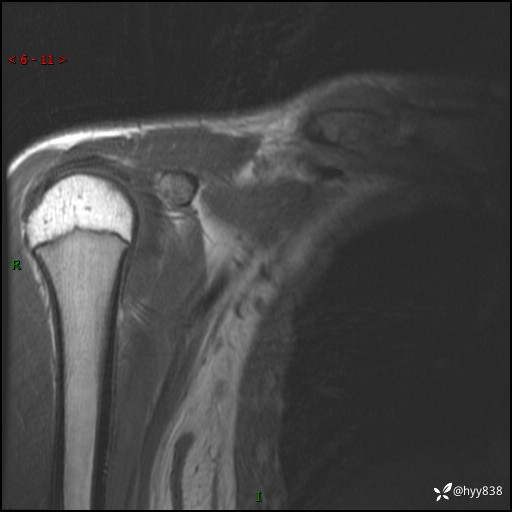

MRI(cor T1WI+T2WIfs+axi T2WIfs)